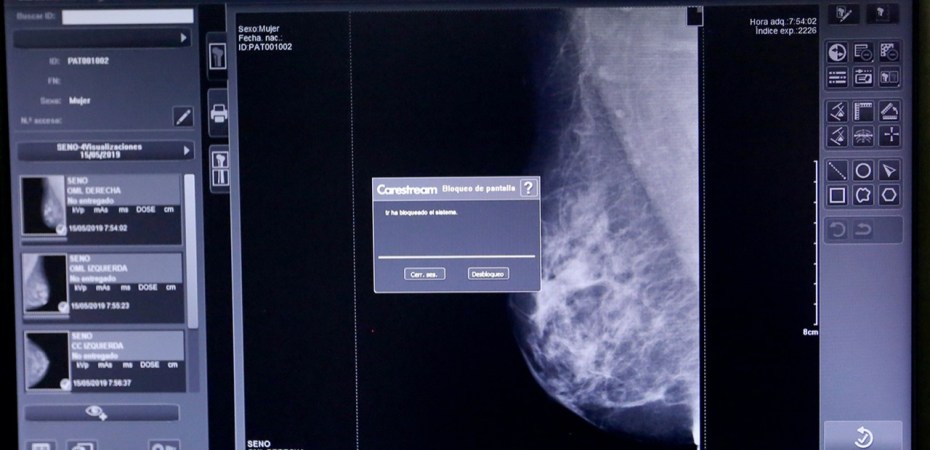

En esta misma sede, dijo Sandra Luz Valdez Ávila, se instauró el Programa Anual de Mastografía, que consiste en establecer una comunicación integral entre esta unidad médica receptora con las clínicas periféricas de la Delegación Regional Zona Sur de la capital del país.

En estas unidades médicas, se les permitirá realizar referencias de pacientes para la toma de mastografías y ultrasonidos complementarios, que serán interpretados por médicos radiólogos con subespecialidad en mama y a quienes lo ameriten se les dará seguimiento mediante toma de biopsia. “Esta estrategia nos permitirá realizar referencias oportunas a hospitales de segundo y tercer niveles de atención”, subrayó.